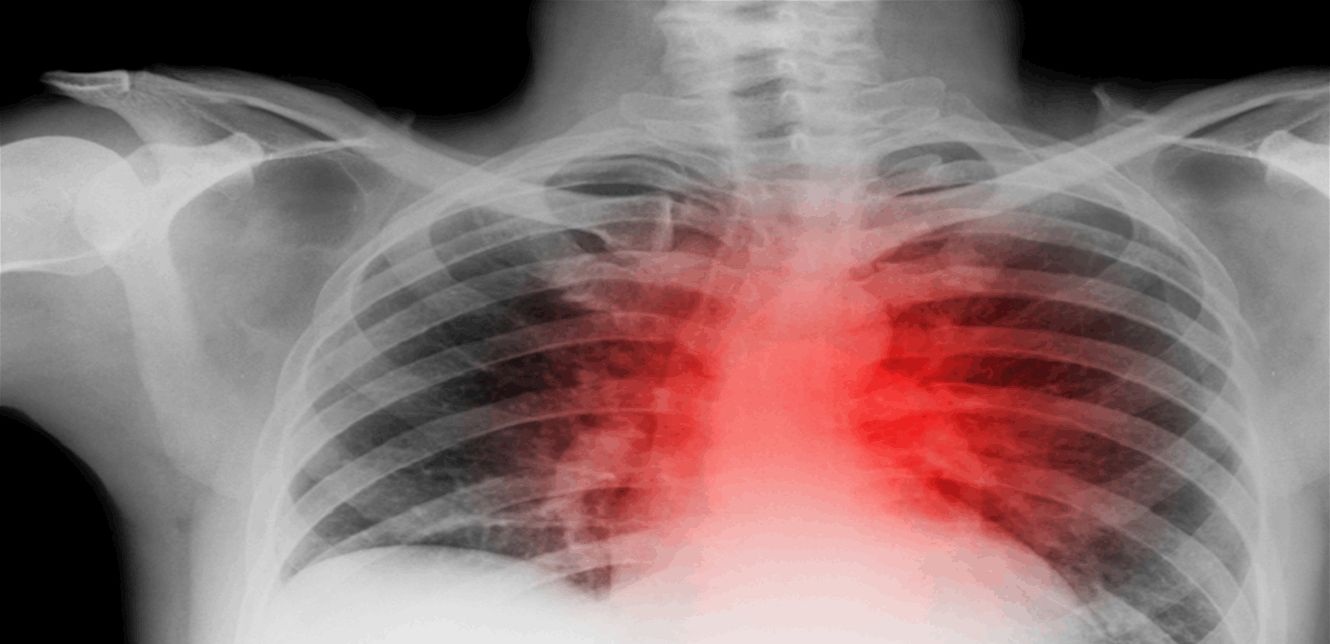

يحدث مرض الانسداد الرئوي المزمن عندما تتلف الرئتين والمجاري الهوائية وتلتهب، وهو غالبا ما يرتبط بالتدخين أو التعرض للمواد الكيميائية والغبار، إلا أن بعض المرضى قد يعانون منه دون سبب واضح.

وفي دراسة أجريت في كوبنهاغن، تم إعطاء 20 مريضا بمرض الانسداد الرئوي المزمن 4 أقراص يوميا تحتوي على جرعات أعلى من فيتامين B3، مقارنة بما هو موجود عادة في المكملات الغذائية. وأظهرت النتائج أن هؤلاء المرضى شهدوا تحسنا ملحوظا في تقليل الالتهابات في رئاتهم.

وأوضح العلماء أن شكلا من أشكال فيتامين B3، ريبوسيد النيكوتيناميد، يعمل على تعزيز جهاز المناعة من خلال تحوله إلى جزيء NAD+ الذي يعتقد أنه يساعد في تقوية النظام المناعي.

وأضاف الدكتور مورتن شيبي كنودسن، الباحث الرئيسي من جامعة كوبنهاغن، أن "الالتهاب في الرئتين قد يؤدي إلى انخفاض وظائفها، ونأمل أن يمهد هذا البحث الطريق لخيارات علاجية جديدة لمرضى الانسداد الرئوي المزمن".

ومع ذلك، أشار العلماء إلى أن الدراسة كانت صغيرة وأن هناك حاجة لإجراء المزيد من الأبحاث لتأكيد النتائج. كما حذروا من أن تناول جرعات كبيرة من فيتامين B3 قد يؤدي إلى آثار جانبية مثل الصداع والتقيؤ وخفقان القلب، لذا ينبغي للمرضى استشارة الأطباء قبل تجربة هذا العلاج. (روسيا اليوم)